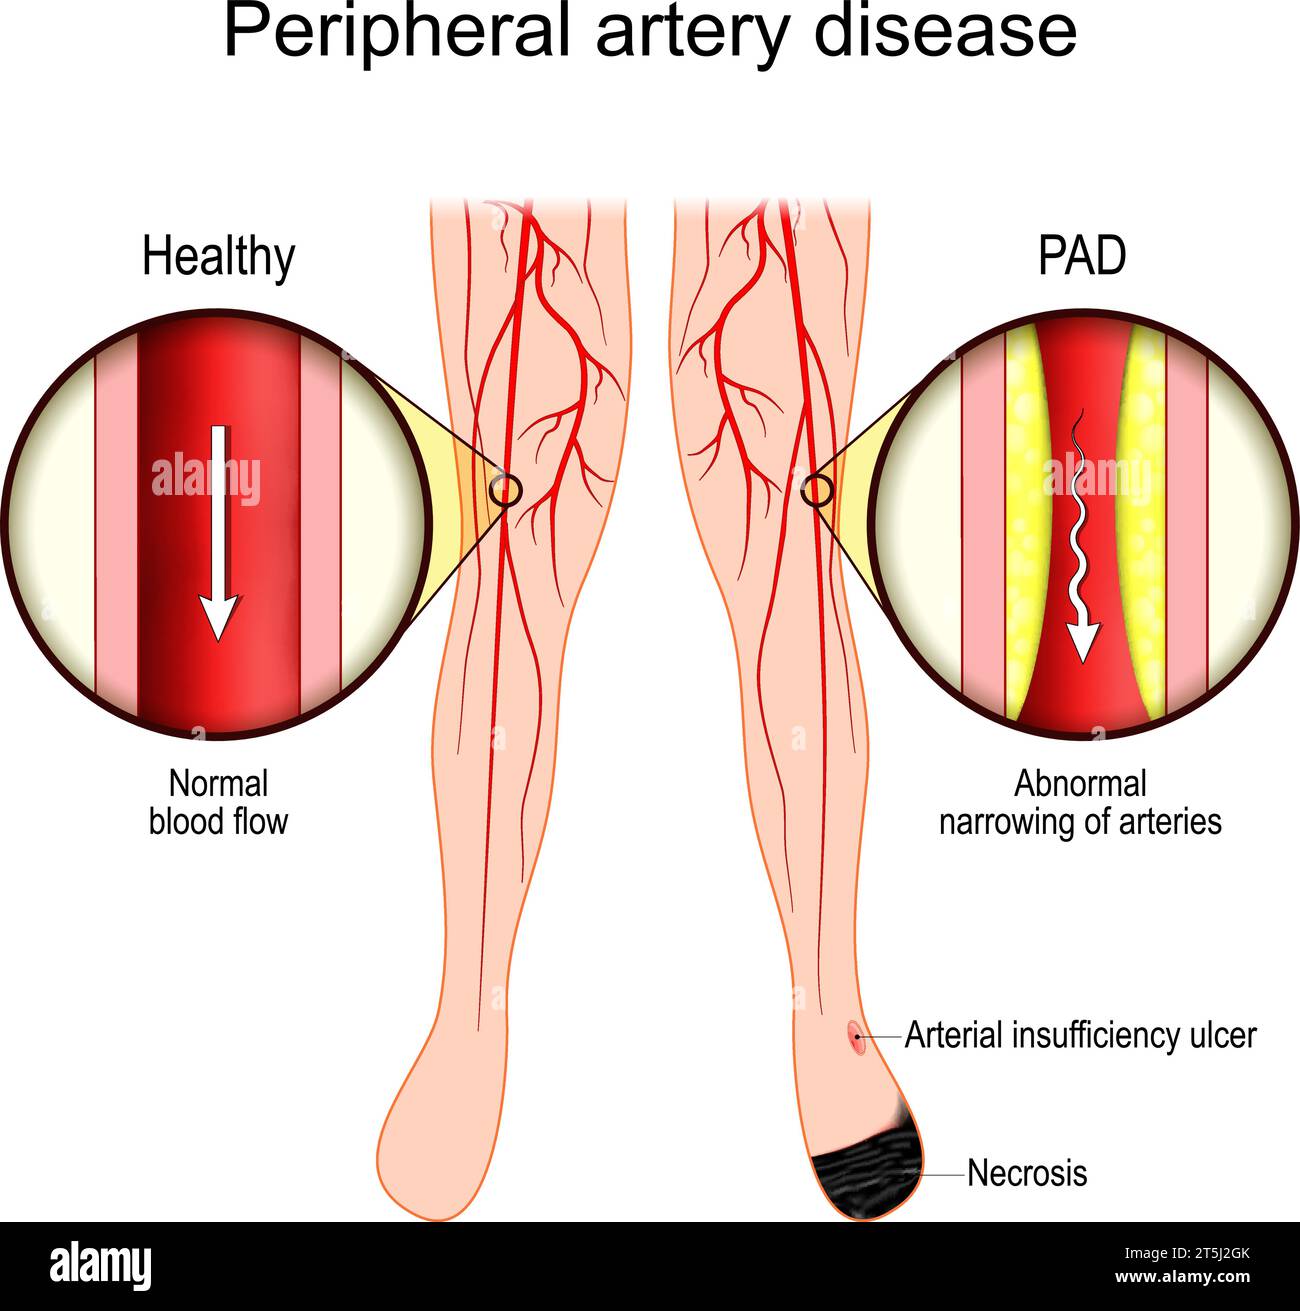

Peripheral Artery Disease. Vascular disease. Cross section of a blood vessel with Atherosclerosis. Close-up of Symptoms of PAD: Necrosis and Arterial Stock Vectorhttps://www.alamy.com/image-license-details/?v=1https://www.alamy.com/peripheral-artery-disease-vascular-disease-cross-section-of-a-blood-vessel-with-atherosclerosis-close-up-of-symptoms-of-pad-necrosis-and-arterial-image571412595.html

Peripheral Artery Disease. Vascular disease. Cross section of a blood vessel with Atherosclerosis. Close-up of Symptoms of PAD: Necrosis and Arterial Stock Vectorhttps://www.alamy.com/image-license-details/?v=1https://www.alamy.com/peripheral-artery-disease-vascular-disease-cross-section-of-a-blood-vessel-with-atherosclerosis-close-up-of-symptoms-of-pad-necrosis-and-arterial-image571412595.htmlRF2T5J2GK–Peripheral Artery Disease. Vascular disease. Cross section of a blood vessel with Atherosclerosis. Close-up of Symptoms of PAD: Necrosis and Arterial